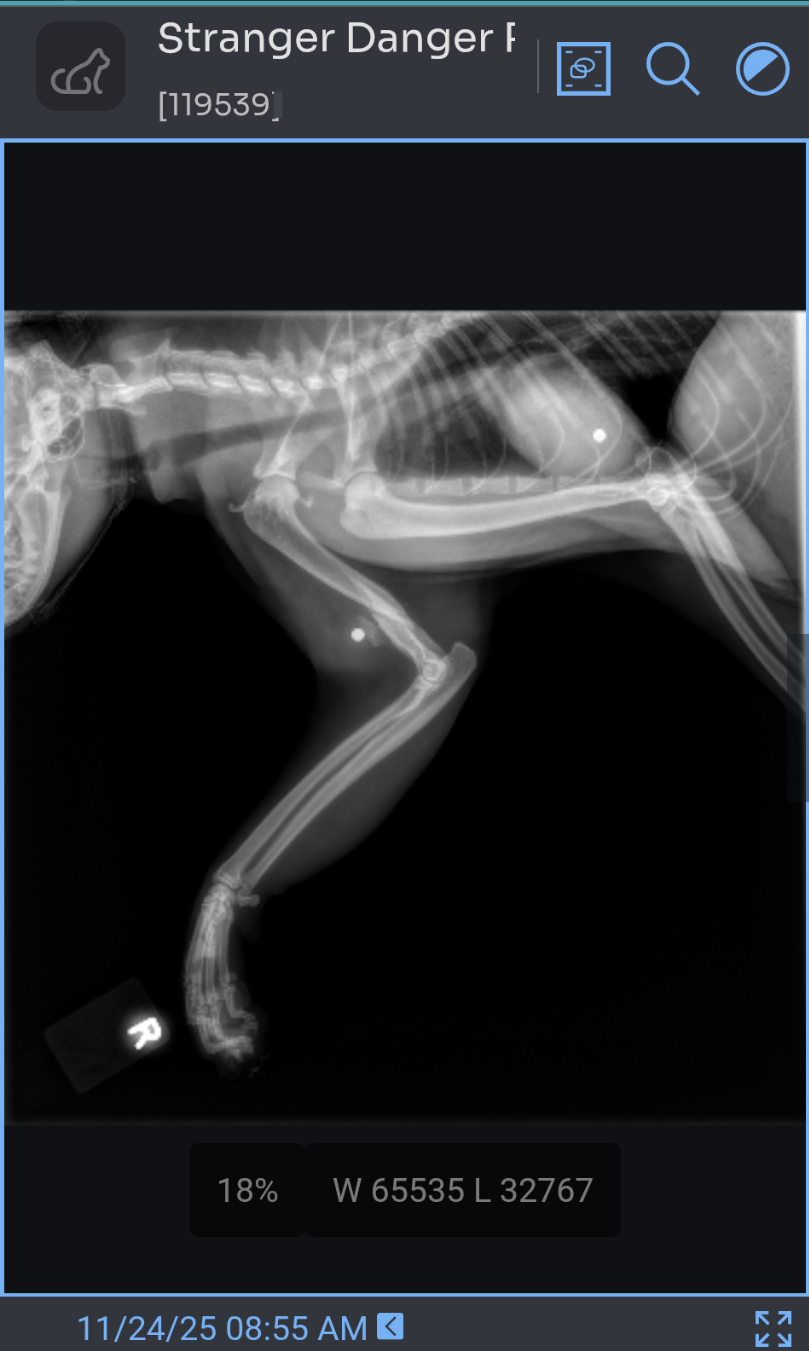

They prescribed painkillers so that we could bring him to our primary care vet the next day to diagnose with X-Rays. The X-Rays revealed that Stranger had been shot twice with a pellet gun. One of the pellets completely broke his humerus (upper arm bone). The extremely professional and helpful veterinarians at Desert Sky Animal Hospital indicated to us that amputation was an option, but strongly encouraged us to consult with an Orthopedic specialist.